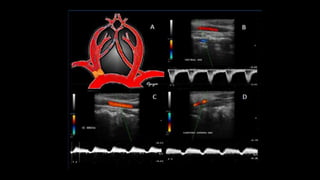

• 4. Doppler espectral:

– En los vasos normales se toman lecturas de las arterias carótida

común, interna y externa.

– En los vasos anómalos se toman lecturas de las zonas de enfermedad

además de lecturas de rutina.

CARÓTIDA COMÚN CARÓTIDA INTERNA CARÓTIDA EXTERNA

• Diámetro 6-8 mm.

• Comparte características de

ambas circulaciones (ext. e int)

• Flujo Anterógrado

• Pulsatilidad Sistólica similar a ACE

• Diástole prolongada similar a ACI

• Diámetro 5 mm.

• Patrón de BAJA RESISTENCIA,

bifásico.

• Rápido incremento en la sístole

• Flujo continuo anterógrado en la

diástole

• Diámetro 3 mm.

• Patrón de ALTA RESISTENCIA,

pulsátil.

• Onda sistólica rápida, pico afilado

con descenso abrupto.

• Menor componente diastólico

• VPS: 78 a 118 cm/s

• VDF: 20 a 32 cm/s

• IR : 0.72 a 0.84

• VPS: 54 a 80 cm/s hasta 100 cms/s en

jóvenes

• VDF: 23a 37 cm/s

• IR : 0.54 a 0.66

• VPS: 57 a 115 cm/s

• VDF: 11 a 21 cm/s

14